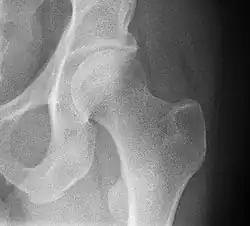

Radiologie conventionnelle

En radiographie standard[3] :

- le bassin de face Debout permet d'évaluer l'épaisseur de l'interligne articulaire et la statique du bassin (recherche d'une bascule du bassin en cas d'inégalité de longueur des membres inférieurs). Ce cliché montre un cintre cervico-obturateur qui doit être régulier ;

- le faux profil de Lequesne permet de mesurer la couverture antérieur et d'évaluer l'interligne articulaire dans le sens antéro-postérieur ce qui est un élément diagnostique plus sensible lors du dépistage de la coxarthrose débutante ;

- le profil chirurgical (d'Arcelin ou de Ducroquet) est l'examen simple ne nécessitant pas la mobilisation de l'articulation, à la recherche d'une fracture du col fémoral ;

- le profil urétral utile dans la recherche d'une ostéonécrose de la tête fémorale.

En radiologie conventionnelle, la coxométrie est la mesure des angles formés par les différentes structures de la hanche et de diagnostiquer des anomalies constitutionnelles ou acquises.